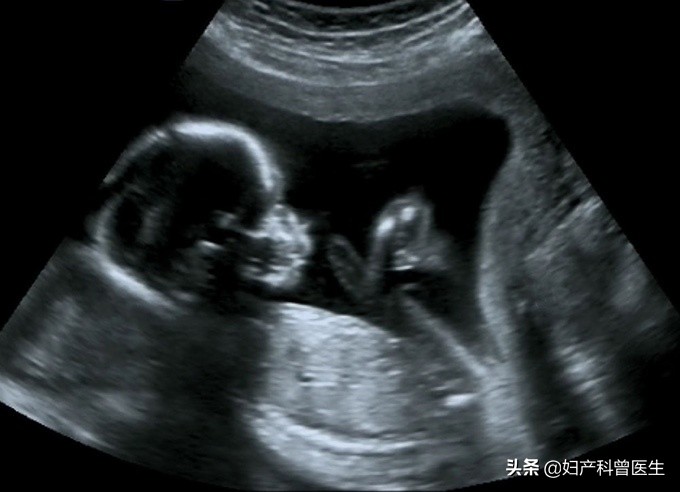

B超显影的胎儿图

到目前为止,正常的做B超检查是没有任何明显的不良反应,也未有过超声检查引起胎儿畸形的报道。因此,孕妈妈们不用担心B超会对胎儿造成什么影响。